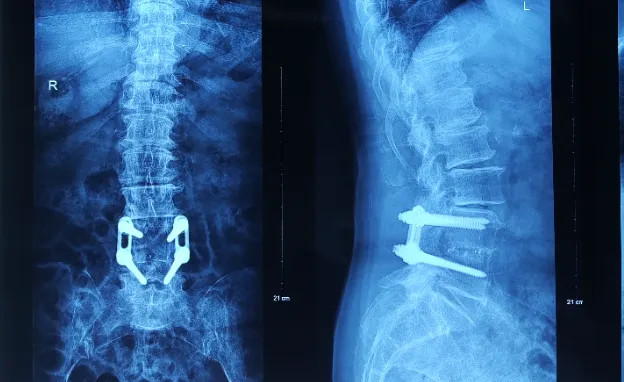

71歲的邱女士與福州有著特殊的醫(yī)患情緣。22年前,她因腰椎滑脫在我院接受L4-5節(jié)段Opus釘板系統(tǒng)復位固定手術(shù),術(shù)后完全康復并保持良好生活狀態(tài)。然而近兩年逐漸加重的雙下肢麻木無力最終發(fā)展為無法站立、二便失禁,輾轉(zhuǎn)粵港澳多家醫(yī)院均因無法處理“古董級”內(nèi)固定而束手無策。

(患者術(shù)前X光片)